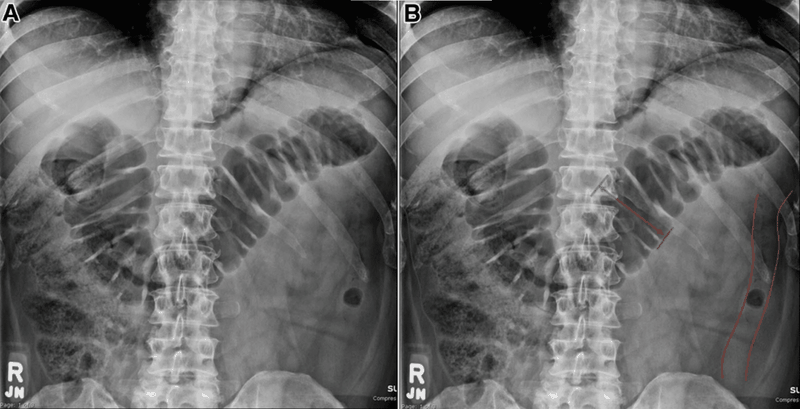

Chụp X quang tắc ruột là một phương pháp hình ảnh y học sử dụng tia X để tạo ra hình ảnh về tình trạng của ruột và các cấu trúc xung quanh. Quá trình này nhằm mục đích đánh giá các vấn đề liên quan đến hệ tiêu hóa, như tắc đường ruột, bóng hơi, hoặc các dạng khối u trong ruột.

Ứng dụng của chụp X quang tắc ruột trong y học nhằm mục đích như chẩn đoán tình trạng tắc ruột ở các bộ phận như ruột non (tiểu tràng) hoặc đại trực tràng. Hiển thị toàn bộ cấu trúc ruột để xem xét các bộ phần như quai ruột, trực tràng và các chi tiết khác.

Khi đã có kết quả chụp X quang cũng như cấu trúc của các bộ phận liên quan trong hệ tiêu hoá, từ đó đưa ra được các đánh giá y tế để bác sĩ phát hiện, chẩn đoán ra được một số vấn đề như viêm nhiễm, polyp, bất thường cấu trúc, tắc nghẽn hay các bệnh lý khác liên quan đến ruột

Bác sĩ có thể chỉ định các phương pháp chụp X quang khác nhau tùy thuộc vào loại và vị trí của tắc ruột. Cần kết hợp nhiều kỹ thuật chẩn đoán hình ảnh cùng với các xét nghiệm khác để có cái nhìn đầy đủ và chính xác về tình trạng của bệnh nhân.